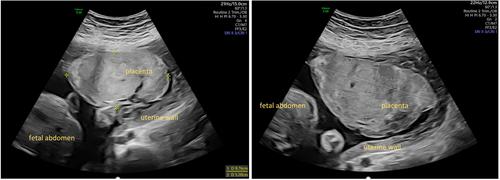

Ia型糖原储存病(GSD Ia)妇女的妊娠和胎盘变化知之甚少。我们报告了两个初产妇与GSD Ia谁都发展先兆子痫和新生儿胎龄小。两个胎盘均表现出形态和宏观异常。疾病特异性组织学特征无法确定,这应促使进一步研究。

Little is known about pregnancies and placental changes in women with glycogen storage disease type Ia (GSD Ia). We report on two primipara with GSD Ia who both developed preeclampsia and whose newborns were small for gestational age. Both placentas showed sonomorphological and macroscopical abnormalities. Disease-specific histological features could not be identified, which should prompt further research.